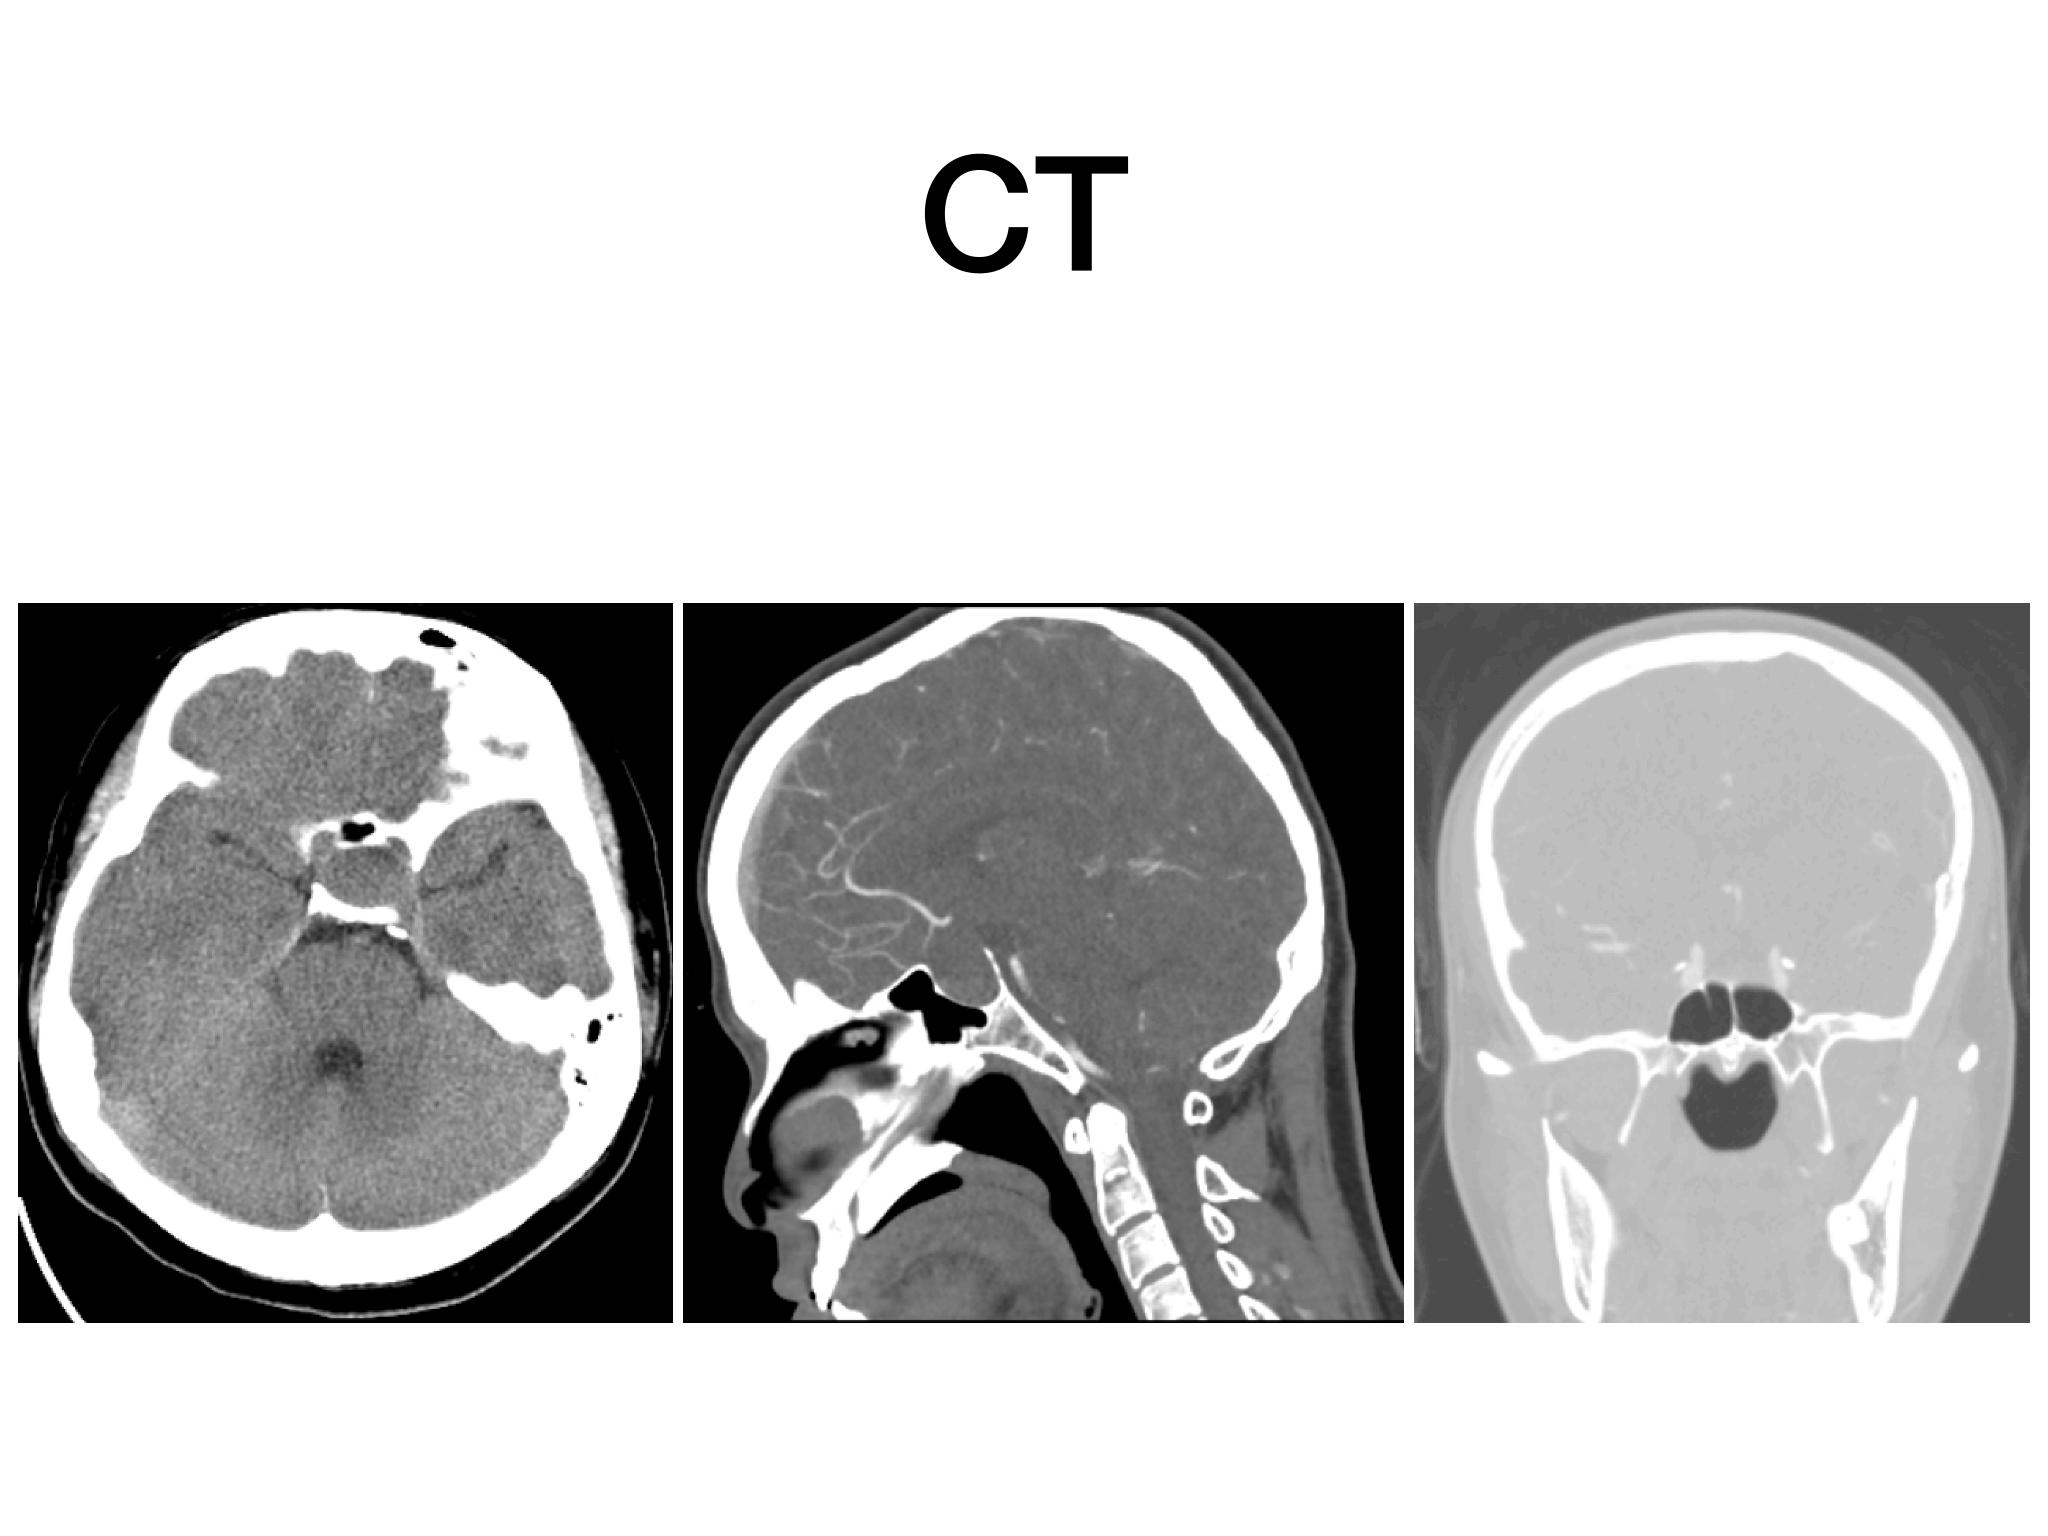

分享一例经鼻内镜泌乳素大腺瘤切除手术,患者青年男性,术前泌乳素>200ng/dl,MR提示大腺瘤合并瘤内出血,手术全切肿瘤,术后泌乳素降至正常,生化缓解,预后良好。